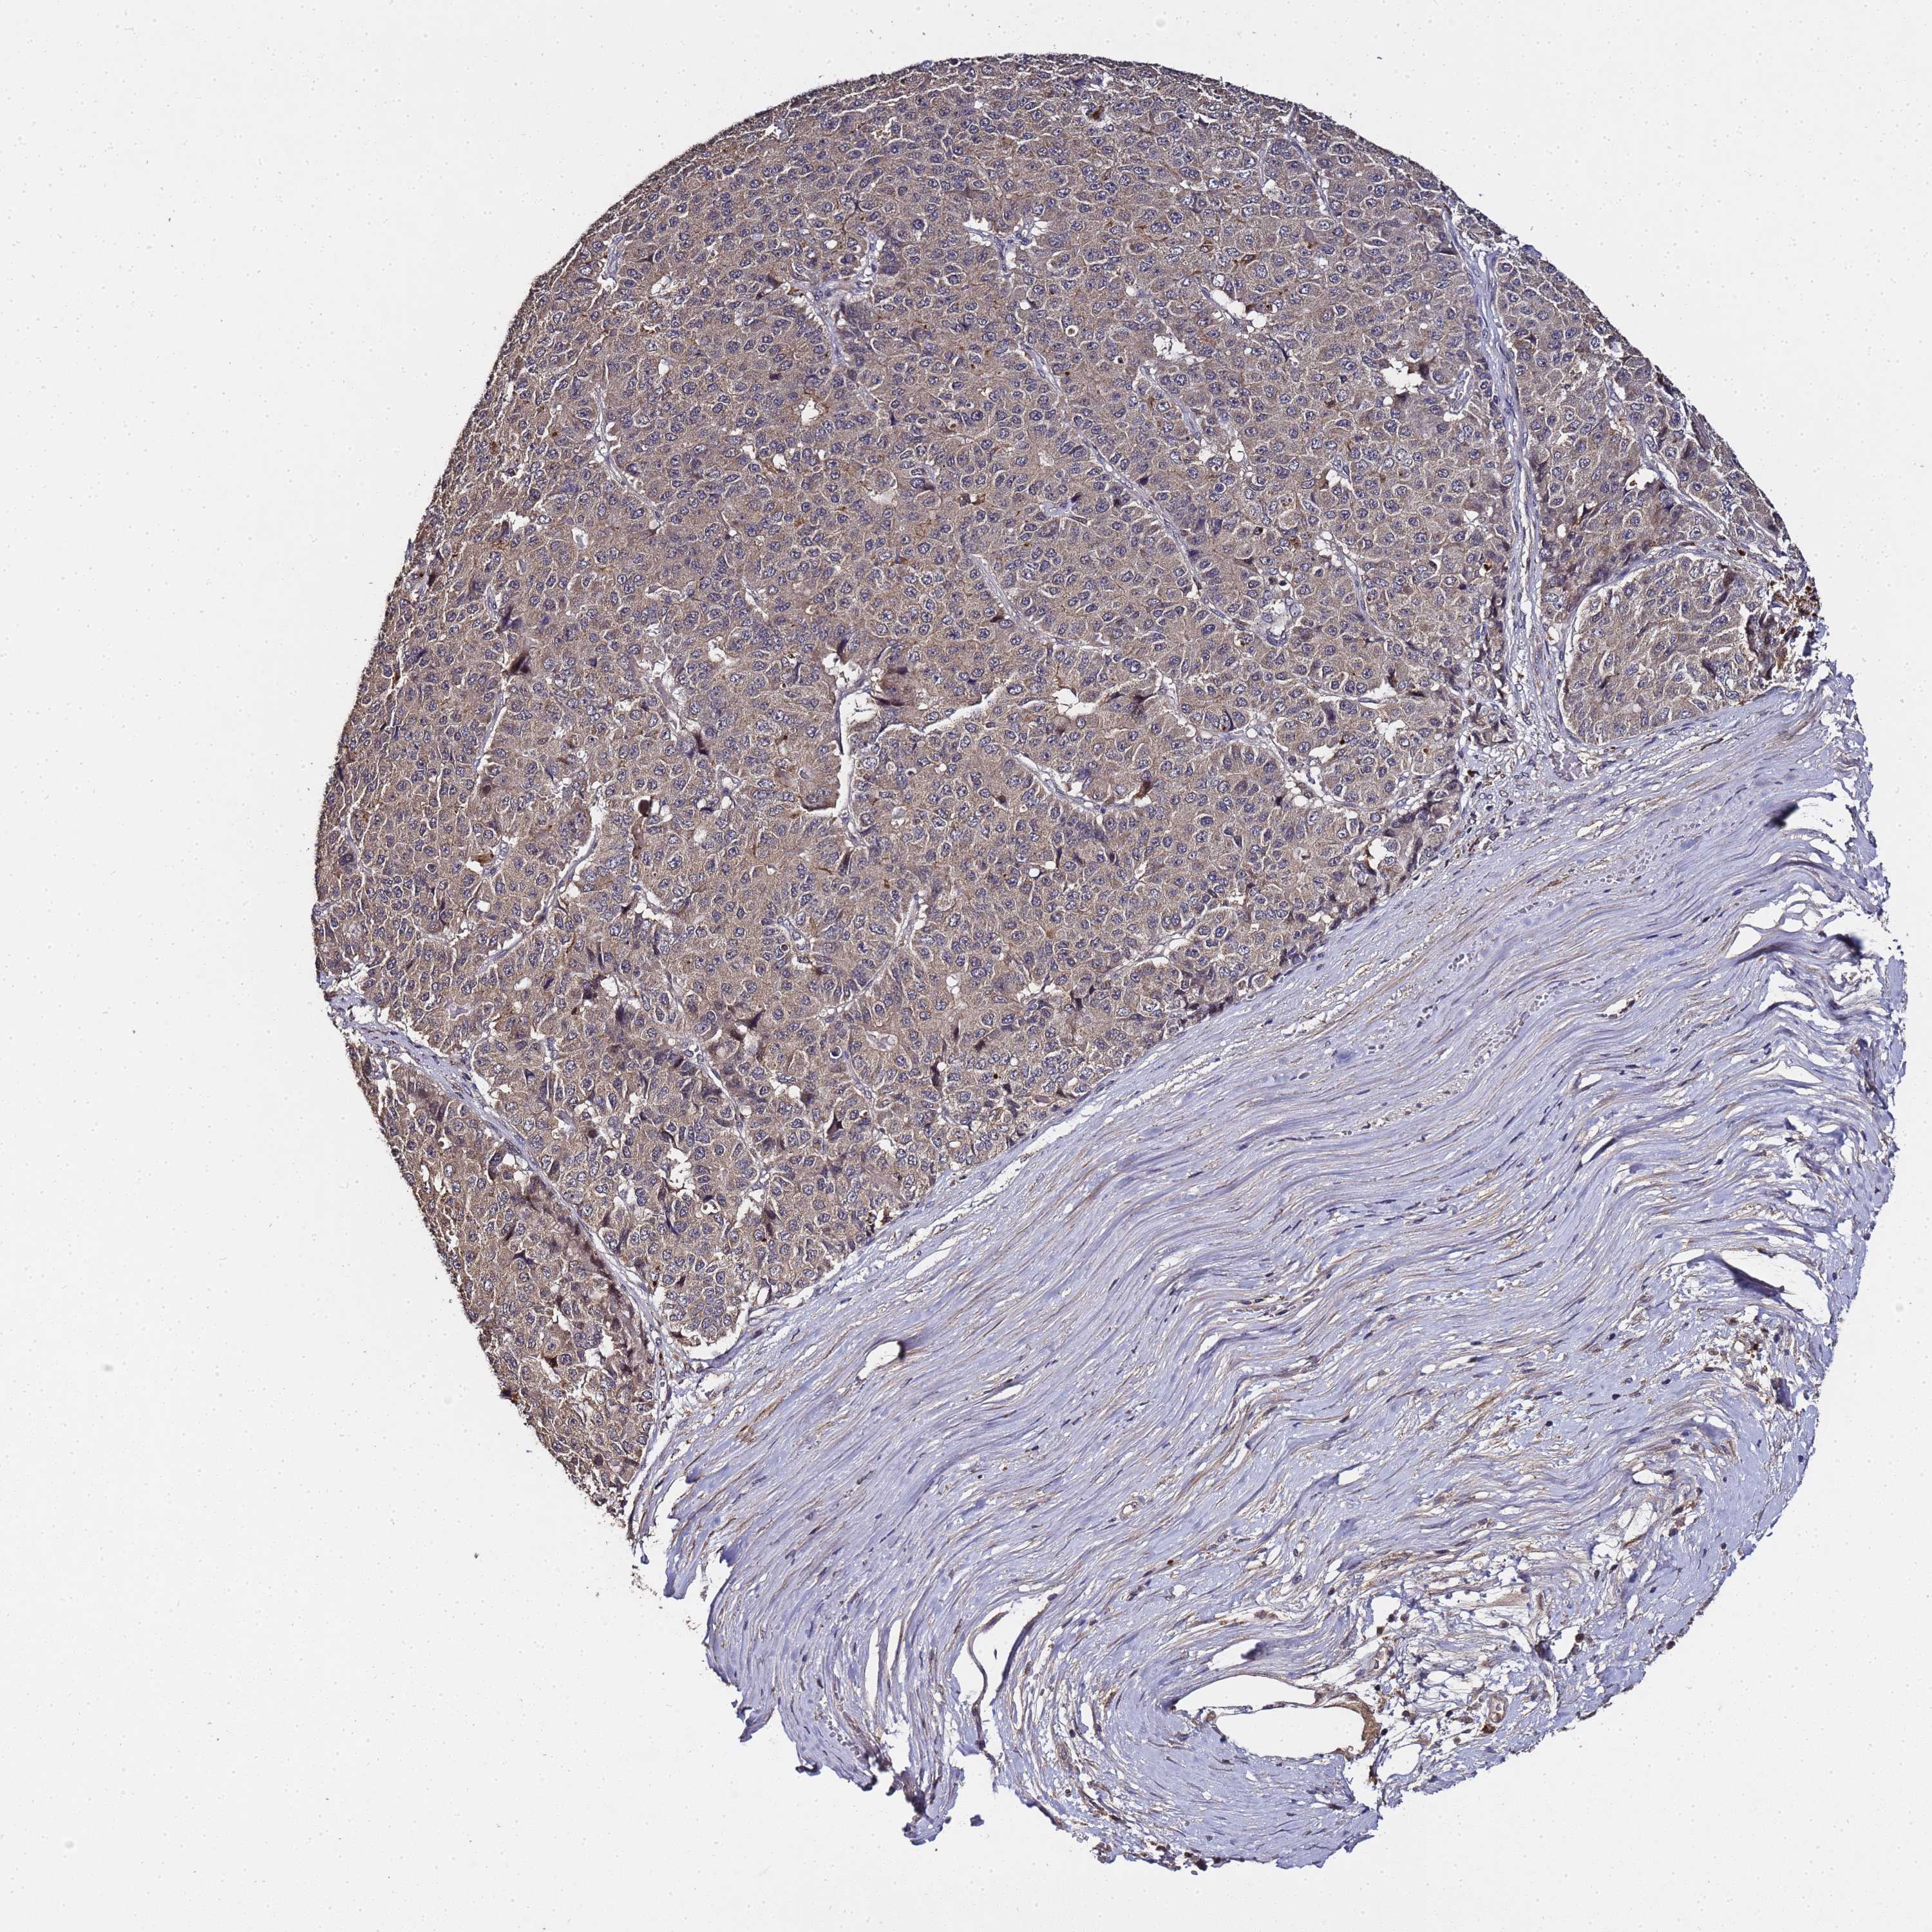

PANCREATIC CANCER - Protein expressioni

A mouse-over function shows sample information and annotation data. Click on an image to view it in a full screen mode. Samples can be filtered based on level of antibody staining by selecting one or several of the following categories: high, medium, low and not detected. The assay and annotation is described here.

Note that samples used for immunohistochemistry by the Human Protein Atlas do not correspond to samples in the TCGA dataset.

Antibody stainingi

Antibody staining in the annotated cell types in the current human tissue is reported as not detected, low, medium, or high, based on conventional immunohistochemistry profiling in selected tissues. This score is based on the combination of the staining intensity and fraction of stained cells.

Each image is clickable and will lead to virtual microscopy that enables deeper exploration of all samples and also displays staining intensity scores, fraction scores and subcellular localization as well as patient and tissue information for each sample.

Antibody HPA042116

Antibody HPA043556

Staining

High

Medium

Low

Not detected

Intensity

Strong

Moderate

Weak

Negative

Quantity

>75%

75%-25%

<25%

None

Location

Nuclear

Cytoplasmic/membranous

Cytoplasmic/membranous,nuclear

Adenocarcinoma, NOS